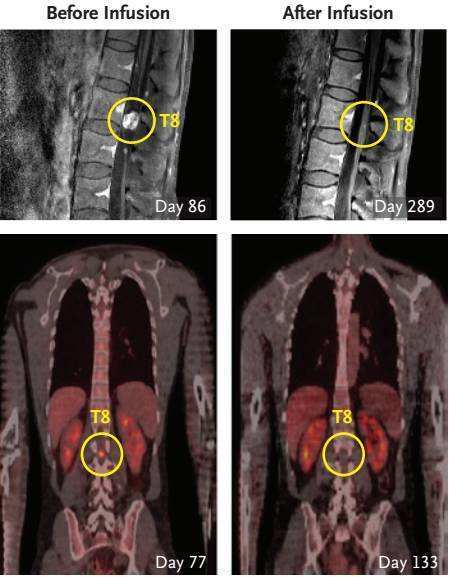

第一疗程持续了6周时间,最大的T1保持原态,而MRI检查显示未经手术移除T4-5以及复发的病灶T6-7生长都在进展。此外,Richard出现了下肢麻痹症状,才发现肿瘤已经有了新的脊柱转移,包括一个直径18mm的“大个子”和几个不到4mm的“小跟班”!这些结果表明, 虽然颅腔内的CAR-T注射治疗能够抑制注射处原发病灶(T1)的复发,却难以控制较远距离的肿瘤。

经过3次注射后(挡急治疗第133天),研究者惊喜地发现所有颅内及脊柱内的肿瘤都在缩小,缩小幅度高达77%!在第5次注射(治疗第190天)时,word哥,所有的肿瘤都消失了!

当然药不能停,Richard后续又接受了5次注射治疗。在巩固治疗阶段,所有肿瘤继续分解,已经无法从MRI或是PET-CT检查中辨认出了。更神奇的是,在进行颅内IL13Rα2-CAR T细胞注射后,脊柱中的两处转移灶也完全被移除。在治疗的108天至284天中,Richard都未系统性服用地塞米松,也由此回到了他最爱的亲人和朋友身边,继续正常的生活。